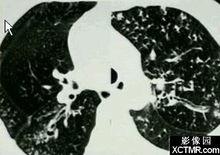

胸部X片檢查顯示肺紋理明顯增多粗亂,在增多的紋理中可見管狀透明區,為管壁增厚的支氣管影,支氣管壁增厚形成兩條平行的線狀陰影,稱為雙軌征或者軌道征,多見於慢支、支擴。

雙軌征CT檢查表現為:CT檢查可以更為清晰地顯示,一般採用常規CT掃描即能顯示,與CT掃描層面平行走行的支氣管可表現為軌道征,,但應注意勿將由呼吸活動或心影搏動引起的血管移動影像認為軌道征。

胸部X線片及CT影像上顯示出管壁增厚的支氣管影,稱為雙軌征或者軌道征,多見於慢支、支擴。